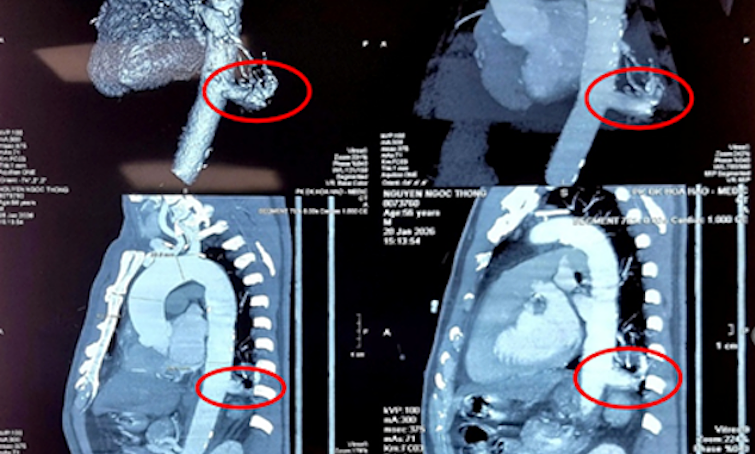

Phần 'phổi thừa' hút máu động mạch chủ người đàn ông suốt 56 năm

Người đàn ông 56 tuổi đi khám sức khỏe bất ngờ phát hiện khối "phổi thừa" bẩm sinh đang hút máu trực tiếp từ động mạch chủ, được bác sĩ Bệnh viện Bình Dân phẫu thuật bằng robot.